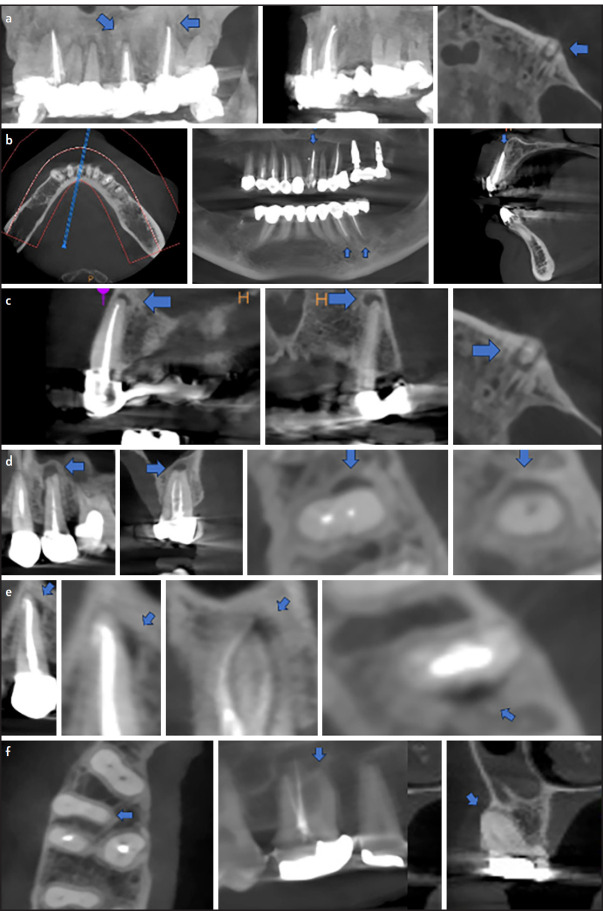

Objective: This study aimed to assess the treatment quality factors associated with the risk of radiographic detection of apical periodontitis (AP) in root-filled teeth (RFT) on CBCT images.

Methods: Two hundred eighty-five CBCT scans of patients (range 18-60, mean 35.1) years old were selected from a pool of CBCT scans which were taken from 2016-2022. Gender and age were recorded. The presence/absence of AP, unfilled canal, perforation, zipping and ledge and homogenous/nonhomogeneous root canal filling (RCF), adequate/inadequate coronal restoration and under/over filled RCF and those within 0-2 mm from the radiographic apex were recorded for RFTs. Kappa was used to assess intra-consensus reliability. Chi-square and Binary logistic regression were used to assess and predict risk factors related to the detection of AP. A significant difference was set at p<0.05.

Results: AP was present in 81.5% of RFTs. No significant difference was present in the AP prevalence in RFT between males and females, maxilla and mandible, right and left sides, RFT with adequate and inadequate coronal restoration and RFT with/without zipping and ledge and between RFT with overfilled and those with RCF end within 0-2 mm from the radiographic apex (p>0.05), respectively. Significantly higher AP prevalence was present in RFT with unfilled canal, perforations, non-homogenous and underfilled RCF (p<0.05), respectively. The odds of AP detection were 2.02, 5.5, 2 and 1.98 times higher in RFT with unfilled canal, perforations, non-homogenous and underfilled RCF, respectively. Intra-consensus reliability was (0.98, 0.95, 0.85, 0.81, 0.88, 0.85 and 0.92) for AP, unfilled canal, perforation, zipping and ledge, homogeneity of RCF, coronal restoration and length of RCF, respectively.

Conclusion: The vast majority of teeth with previous root fillings presented with AP. AP detection risk was significantly higher in root-filled teeth with perforation, non-homogeneous, and underfilled root canal filling. Other factors do not influence the radiographic detection of AP in CBCT images. (EEJ-2024-02-042).